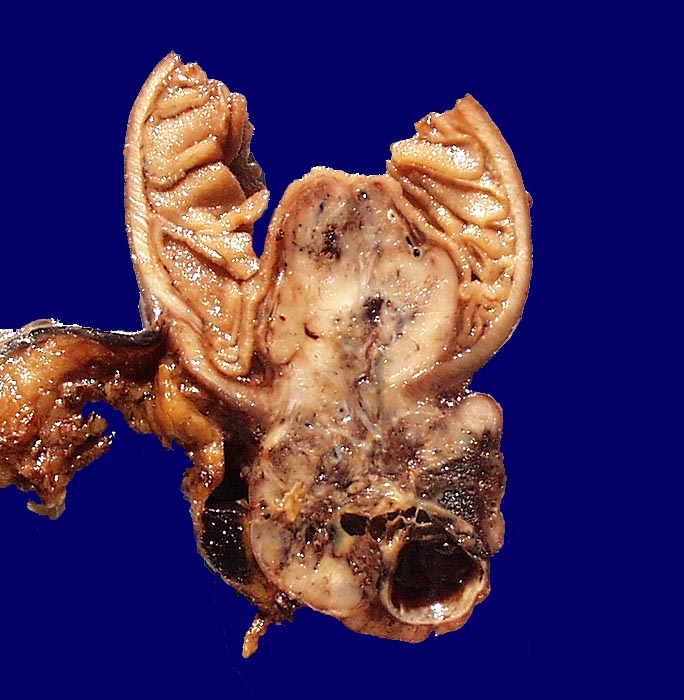

Makroskopisch imponieren kleine Tumoren als peritoneale, intramurale oder submuköse Knoten. Grössere Tumoren wölben sich oft vor und können ulzerieren. Die Schnittfläche ist weisslich und kann Einblutungen, Zysten, Fibroseareale oder Nekrosen aufweisen. Histologisch werden Spindelzelltyp (70%), Epitheloidzelltyp (20%) oder gemischtzelliger Typ (10%) unterschieden. Der histologische Subtyp scheint keinen Zusammenhang mit zugrundeliegender Mutation, Therapieansprechen und Prognose zu haben. Gelegentlich sind vor allem die kleineren Tumoren zellarm und kollagenreich.

• Scharf begrenzter kugeliger Tumor in der Submukosa des Magenantrums

• Über dem Tumor entzündungsfreie Antrumschleimhaut mit partiell reepithelialisiertem oberflächlichem Ulkus (Quellungsfibrinoid).

• Herdförmig pseudozystische Auflockerung des Tumorgewebes.